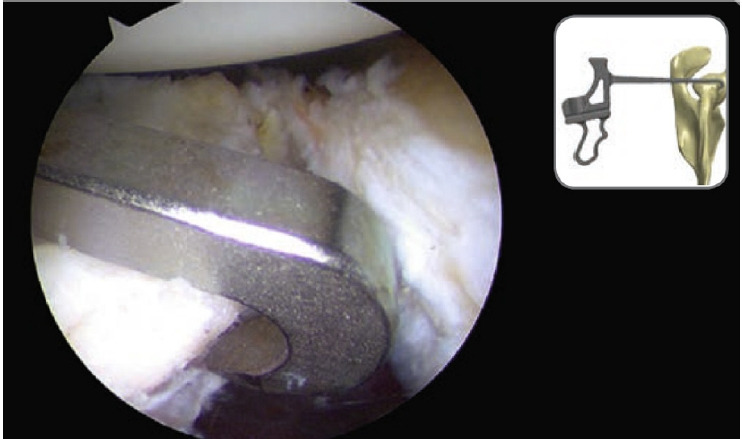

Methods: Anterior glenoid bone block reconstruction with suture buttons utilizing a posteroanterior reference guide was performed in 10 fresh frozen cadavers via a posterior portal. Bullets were inserted in predefined superior and inferior guide holes via percutaneous incisions to facilitate posteroanterior drilling. Looped guide wires were used to deliver suture buttons from anterior to posterior positions. The shoulder joint was disarticulated and the infraspinatus sharply elevated until the suprascapular nerve was visualized. Four independent static measures of the shortest distance from the superior drill sleeve to the lateral aspect of the suprascapular nerve were recorded.